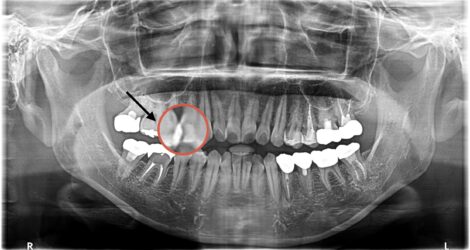

└4MTA

今回はMTAセメントの症例をご紹介します?

☆クリーニングで虫歯が見つかり処置

☆左上4

?MTAセメント?

・マイクロ下で処置、動画も撮影

・処置時間1時間

・¥55,000

【担当医】北野 展久